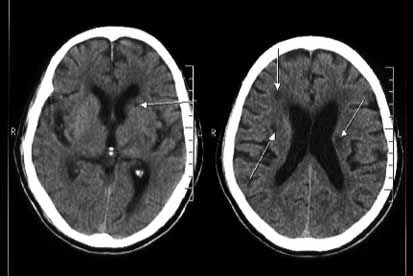

腔隙性脑梗死或腔隙卒中是指大脑半球或脑干深 部的小穿通动脉,在长期高血压基础上,血管壁发生病变,最终管腔闭塞,导致缺血性 微梗死,缺血、坏死和液化的脑组织由呑噬细胞移走形成空腔,故称腔隙性脑梗死。主 要累及脑的深部白质、基底节、丘脑和脑桥等部位,形成腔隙状梗死灶。部分病例的病 灶位于脑的相对静区,无明显的神经缺损症状,放射学检查或尸检时才得以证实,故称 为静息性梗死或无症状性梗死。腔隙性脑梗死约占全部脑梗死的 20%~30%。

腔隙性脑梗死的主要病因为高血压导致小动脉及微小动脉壁脂质透明变性,管腔闭 塞产生腔隙性病变。舒张压增高对于多发性腔隙性脑梗死的形成更为重要。病变血管多 为直径 100~200μm 的深穿支,如豆纹动脉、丘脑穿通动脉及基底动脉旁中央支,多为终 末动脉,侧枝循环差。高血压性小动脉硬化引起管腔狭窄时,继发血栓形成或脱落的栓 子阻断血流,会导致供血区的梗死。多次发病后脑内可形成多个病灶。 腔隙性梗死灶呈不规则圆形、卵圆形或狭长形,直径在 0.2~20mm,多为 3~4mm。病灶常位于脑深部核团(壳核约 37%、丘脑 14%、尾状核 10%),脑桥(16%)和内囊 后肢(10%),内囊前肢和小脑较少发生。